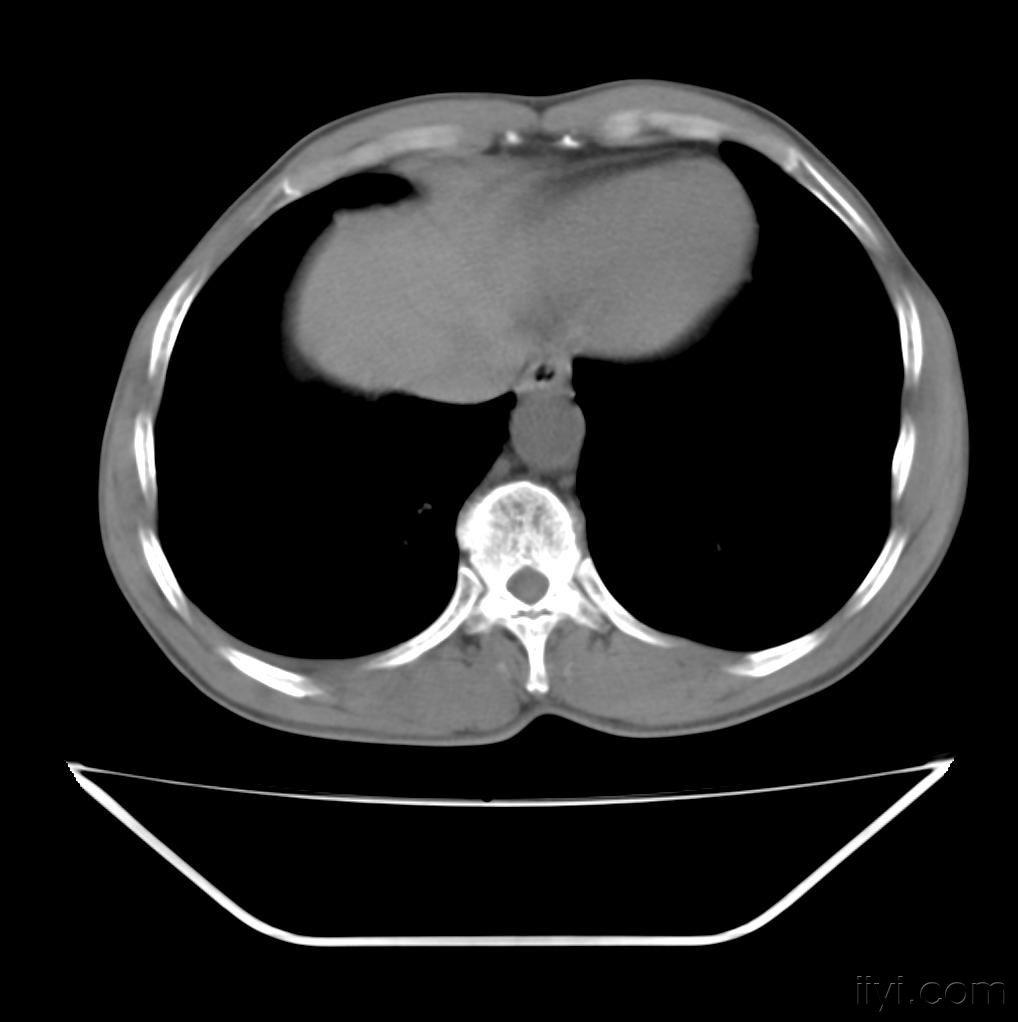

正常胸部ct肺段及淋巴结分区

肺癌ct片!